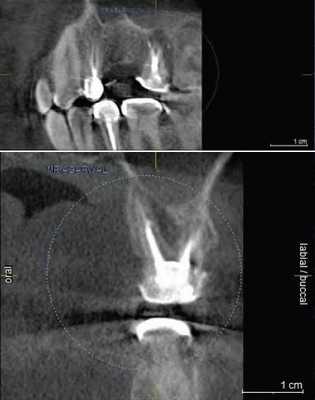

3. Переломы корня

Достаточно тщательно изучена польза и важность КЛКТ в процессе постановки диагноза и ведения зубоальвеолярной травмы, особенно переломах корня, люксации, смещения и переломе альвеолярного отростка.

КЛКТ найдено применение конкретно при диагностике перелома корня зубов.

(Фото 7,8) Высокая важность КЛКТ в определении вертикальных и горизонтальных переломов корня были также описаны в литературе. Элиминация наложения анатомических структур позволяет клиницисту четко анализировать перелом. Вдобавок, 3D реконструкция может быть осуществлена как зубочелюстной системы, так и альвеолярной кости.

Фото 7: Перелом корня в эндодонтически леченом верхнем правом втором моляре

А: ОПГ, показывающая ранее леченые каналы верхнего правого первого моляра

B: Аксиальное изображение, демонстрирующее линию перелома по небному корню

С: Секционный снимок, показывающий косую линию перелома небного корня

Фото 8: горизонтальный перелом правого верхнего центрального моляра

А: 3D изображение, демонстрирующее линию перелома у соединения средней и апикальной трети корня

B: Аксиальный снимок, показывающий горизонтальную линию перелома в передней части верхнего правого центрального резца

С: Косая линия отлома, распространяющаяся от мезиального каря центрального резца на секционном снимке.

5. Послеоперационная оценка

Мониторинг заживляющего процесса апикальных поражений является важным аспектом в послеоперационном этапе эндодонтии. Также адекватная обтурация корневого канала - это важная детерминанта эндодонтического успеха. Можно заявить, что КЛКТ весьма полезна как при начале лечения, так и при отслеживании последующего состояния зуба. Sogur сообщает, что изображения, полученные при обычном рентгенологическом исследовании в послеоперационном периоде являются более информативными, чем КЛКТ. Этот факт ученый объясняет наличием большого количества артефактов на снимках КЛКТ, обусловленных присутствием гуттаперчи и силлера в каналах (Фото 9).

Фото 9: Артефакты обтурированных корневых каналов

Применение КЛКТ в определение точного места перфорации и ее роли в дальнейшем плане лечения проиллюстрировал Young (Фото 10).

Фото 10: Перфорация корня, хорошо заметная на аксиальном снимке